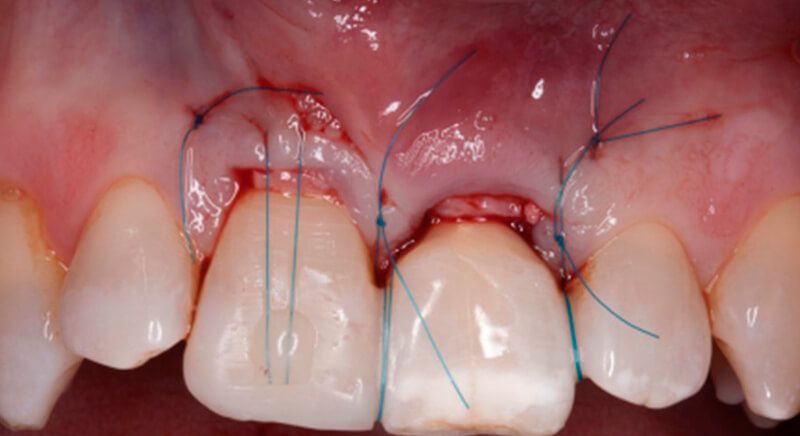

The guided surgery was performed by lifting a full thickness mucoperiosteal flap. A Biomimetic Ocean CC implant, diameter 3.5mm and length 10mm, was inserted using the surgical guide in the ideal three-dimensional position and the defects were regenerated with xenograft and reabsorbable membrane, the nasopalatine duct on the palatine side and the area of dehiscence on the vestibular.

During the same surgical intervention, a short 3mm Avinent healing abutment was positioned and fully covered by the flap. Primary closure was completed and we waited 6 months for the bone graft to mature.

After 6 months of healing, a minimum crestal incision was made to change the 3mm abutment underneath for a 5mm abutment that would be exposed to the oral medium.